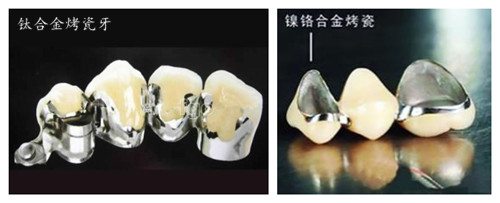

材料没有选择正确,会导致患者对部分材料的过敏,比如:镍铬合金烤瓷牙就会对部分人群有过敏反应。医生技术不佳,很可能就会出现边缘不齐等现象,造成口腔组织受损,危害到口腔健康。

康贝佳口腔医师提醒:烤瓷牙修复选择材料很重要。目前烤瓷牙常用的安全材料有贵金属烤瓷牙,钛合金烤瓷牙,全瓷牙等,比较注意美观及牙齿形态的顾客,建议选择更接近真牙的全瓷牙材料。当然选择临床经验丰富的专业医生也同样重要。>>>我是这种情况,在线咨询